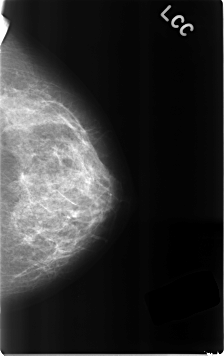

C_0306_1.LEFT_CC

LEFT_CC LINES 4616 PIXELS_PER_LINE 2904 BITS_PER_PIXEL 12 RESOLUTION 50 NON_OVERLAY